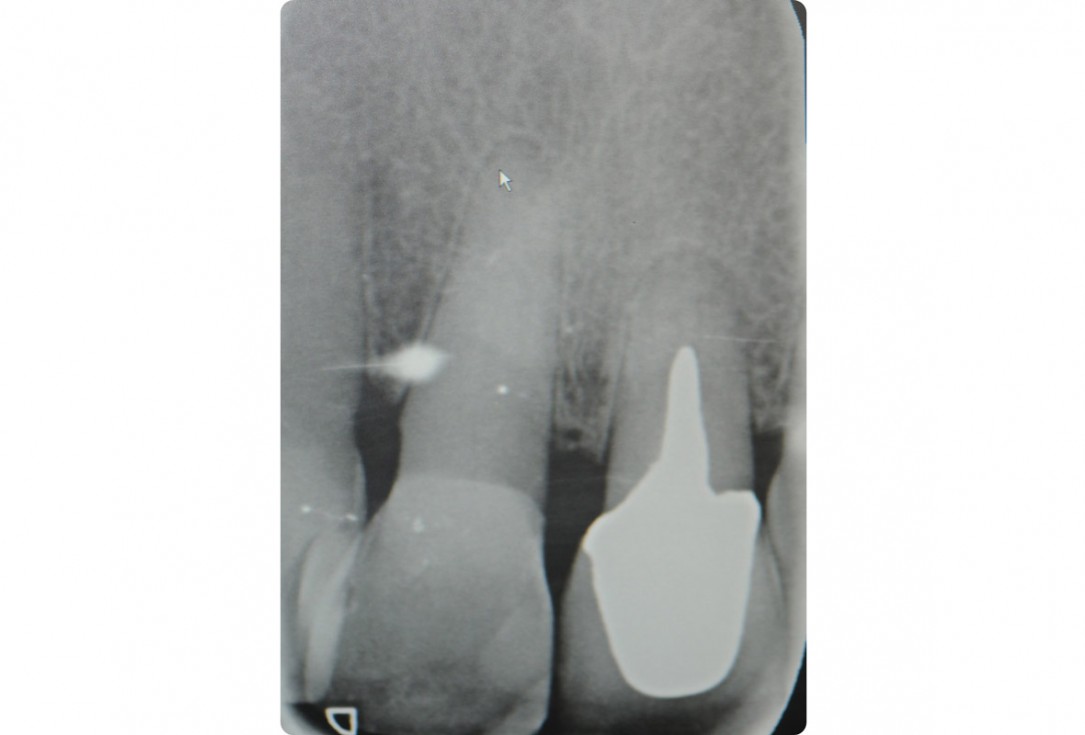

3/18 - Enoral periapical X-ray showing poor root dimensionTooth extraction and socket sealing with mucoderm® - Dr. A. Rossi